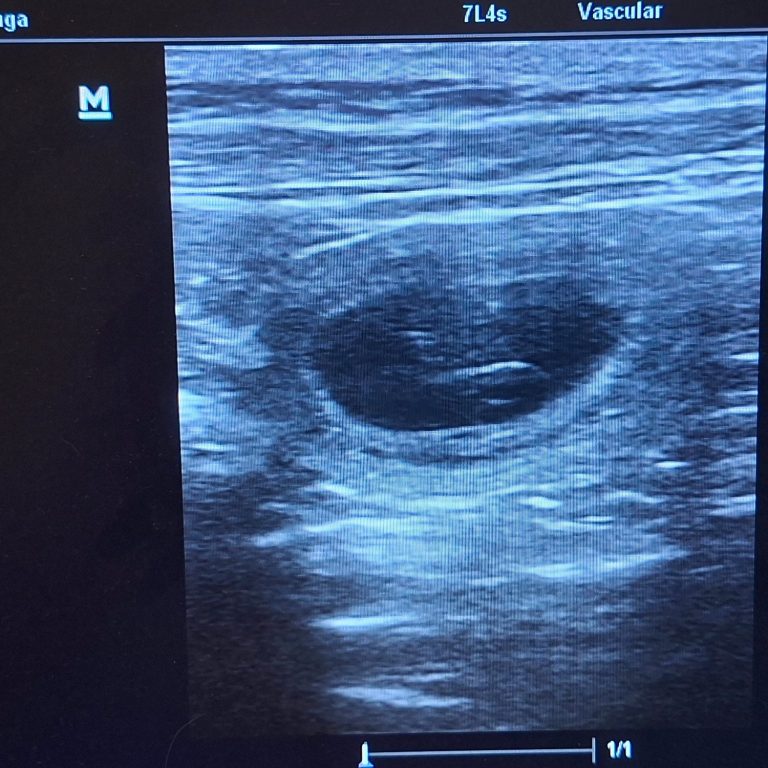

Endlich hatten wir den ersten Ultraschall und wir haben tolle Neuigkeiten

!!Kuba ist trächtig!!

Die letzten Tage waren für mich sehr sehr hart. Die Spannung war kaum auszuhalten. Ich wollte es jetzt endlich bestätigt haben, dass unsere Kuba trächtig ist. Ihr Verhalten und ihr Körper haben sich aber schon sehr verdächtig verändert. Sodass es heute eigentlich klar war, dass wir mit dem Ultraschall fündig werden. Wir haben nur einen kleinen Bereich geschallt und auch nicht lange, damit es für sie nicht zu anstrengend wird. Uns war nur wichtig zu sehen, dass es geklappt hat und die Kleinen leben. Alle Herzchen die wir gefunden haben schlugen ganz stark und alles sieht sehr gut aus.